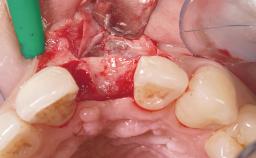

Immediate Placement of an Implant in a Maxillary Right Central Incisor Site

A 30-year-old female patient was referred to the office for the treatment of tooth 11. Her chief concern at the initial visit was to inquire, “Why is my tooth pink?” Upon clinical examination, it was determined that tooth 11 had a previous history of trauma and that the clinical crown had become noticeably pink in color as a result of internal resorption. This diagnosis was confirmed radiographically, indicating a large radiolucency involving the central and distal portions of the clinical crown. It was determined that restoration of this tooth was not possible, and that extraction was indicated. The presence of a mid-line diastema, which the patient wanted to reproduce, directed the treatment plan for tooth replacement utilizing a dental implant.

Bone Augmentation Horizontal|Simultaneous

Augmentation Materials Autogenous chips|Membrane

Bone Volume Sufficient, with intact walls